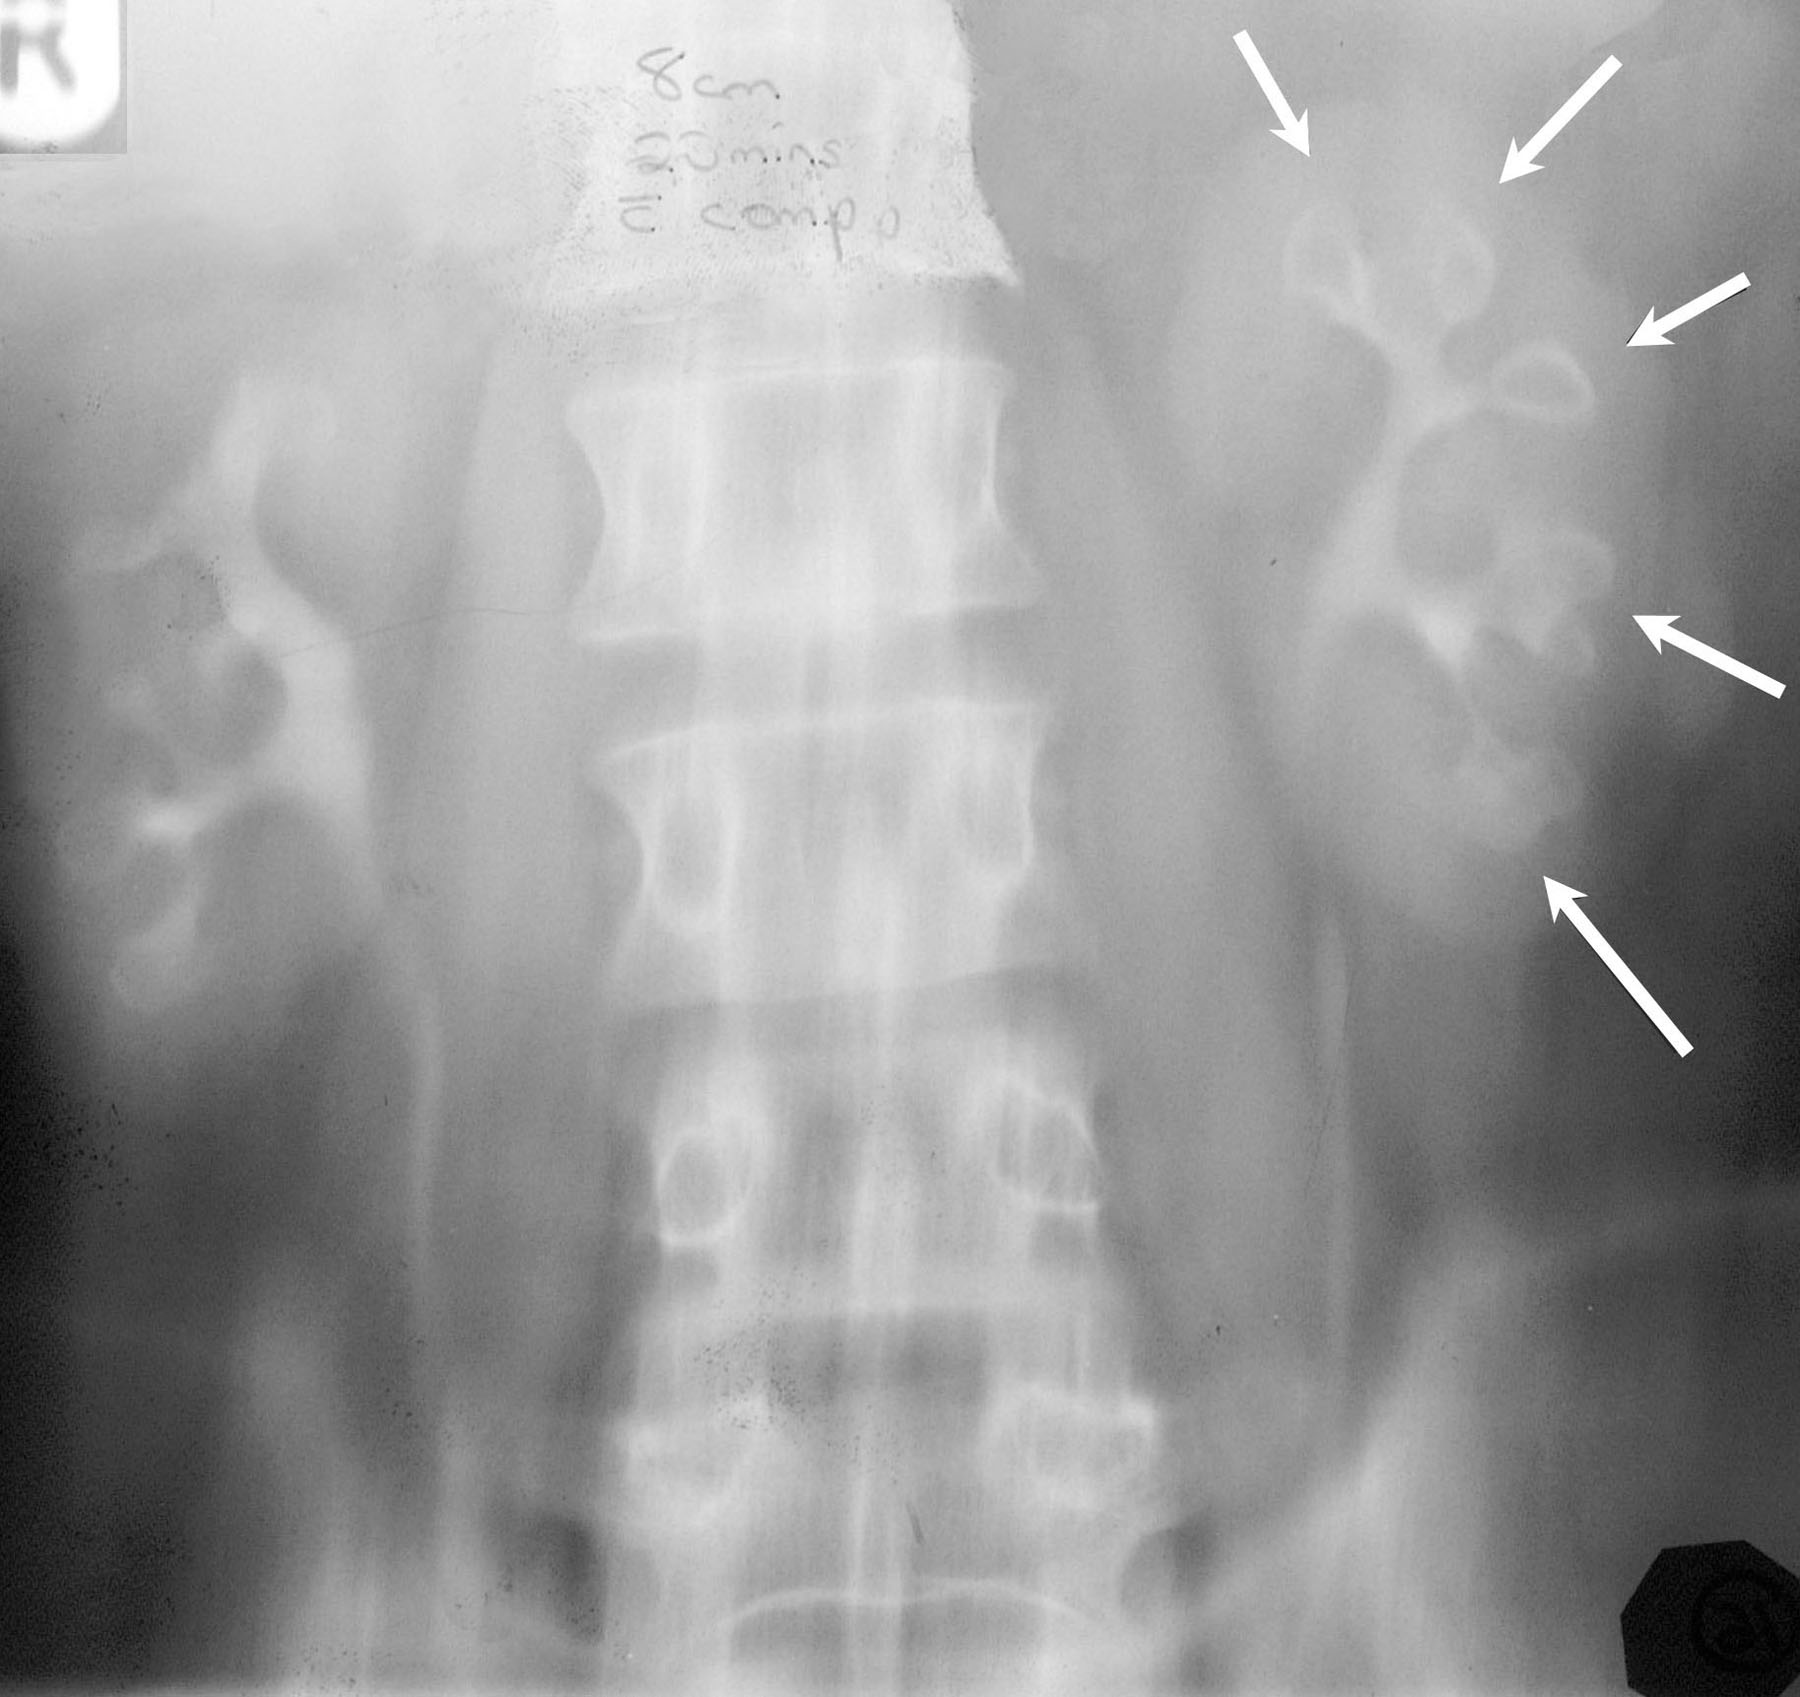

Signo de necrosis papilar en la urografía. La papila desprendida se ve como una defecto de repleción radiotransparente que ocupa la totalidad de su cáliz salvo un fino contorno radioopaco (flechas).

Tomografía simple que muestra varias papilas necrosadas con el signo del anillo.